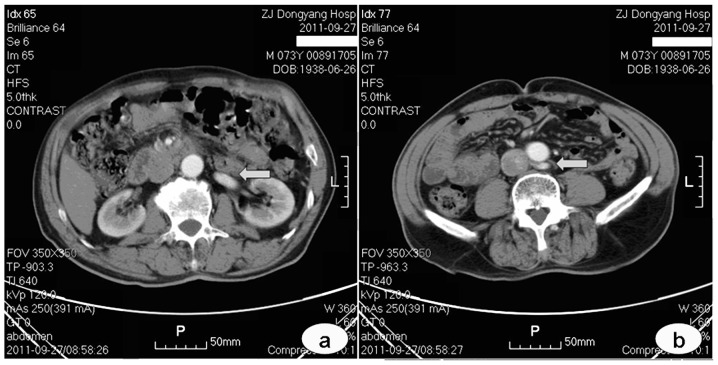

High-resolution digital imaging for detailed cellular analysis.